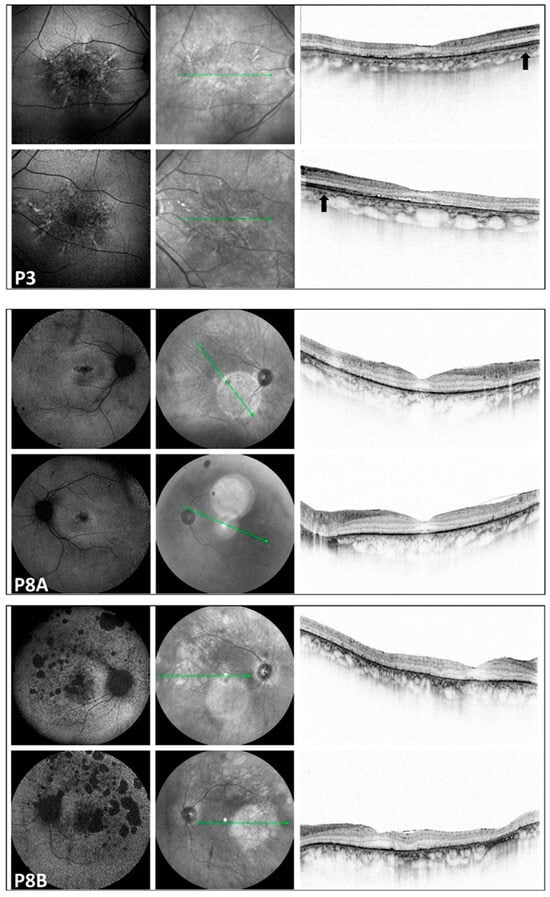

Figure 3. Multimodal imaging of the pedigree: P3: LOMD patient; P8A and P8B: RCD patients. Images of both eyes (right in the superior, left in the bottom rows) in respective order from the top, presenting a blue autofluorescent and an infrared image, as well as a macular OCT scan, respectively, from the right side in each row. FAF pictures of patient P3 with late-onset macular dystrophy show a diffuse pattern of dystrophy-like hypoautofluorescence, and macular OCT shows disruption of the RPE-ellipsoid zone complex. On the OCT image of P3, the arrow indicates preserved retinal layers. In the corresponding region of patients P8A and P8B, severe neuroretinal degeneration is evident. Significant disruption of the RPE-ellipsoid zone complex is observed in both the central and peripheral retina. All three patients with macular involvement exhibited a normal appearance of the optic disk and vessels. Only P3 showed some small, round pigmentation spots at the periphery; otherwise, the periphery appeared normal in the patients with macular involvement. The green line indicates the locations of the scans shown in Figure 3.

FAF imaging was performed in all patients (nine out of nine). A high degree of interocular symmetry was evident in all cases. In one case (P1), a large confluent hypoautofluorescent area was present in the posterior pole, with a small central island that remained preserved. In P2, small hyperautofluorescent spots were observed alongside a large hypoautofluorescent atrophic area, which did not affect the fovea. In the case of LOMD (P3), small perifoveal hyperautofluorescent regions were identified in the posterior pole.

FAF imaging revealed a bull’s-eye phenomenon, characterized by an extensive perifoveal hypoautofluorescent ring. This finding was noted in two cases (P5 and P7). Additionally, one case (P4) exhibited scattered tiny hypoautofluorescent and hyperautofluorescent dots. Three cases (P6, P7, and P8B) showed small or large hypoautofluorescent spots, while another patient (P8A) presented a moderately sized cluster of tiny pinprick hypoautofluorescent dots in the foveal area.

In the peripheral regions of the five RCD patients, small and large patchy hypoautofluorescent spots were observed in three cases (P4, P7, and P8B). Additionally, one patient (P8A) exhibited small hypoautofluorescent dots, while another patient (P5) displayed both small hypoautofluorescent and hyperautofluorescent dots.

3.5. Optical Coherence Tomography (Figure 1, Figure 2 and Figure 3)

We also identified two previously unreported intronic/splice-region variants. P2 (COD phenotype; Figure 1) carried c.783G>A in trans with the novel canonical splice acceptor variant c.349-1G>A, which is expected to disrupt splicing. P3 (LOMD phenotype) carried the novel intronic variant c.1168-10A>G, predicted in silico to weaken the native acceptor site and create a cryptic splice site with an in-frame insertion of three amino acids; notably, her offspring (P8A, P8B) were homozygous for c.1168-10A>G and exhibited an RCD phenotype (Figure 3). This intrafamilial variability underscores the substantial phenotypic heterogeneity of CDHR1-associated retinopathy and supports the need for transcriptional studies to confirm splicing consequences and clarify genotype–phenotype relationships for these novel variants.